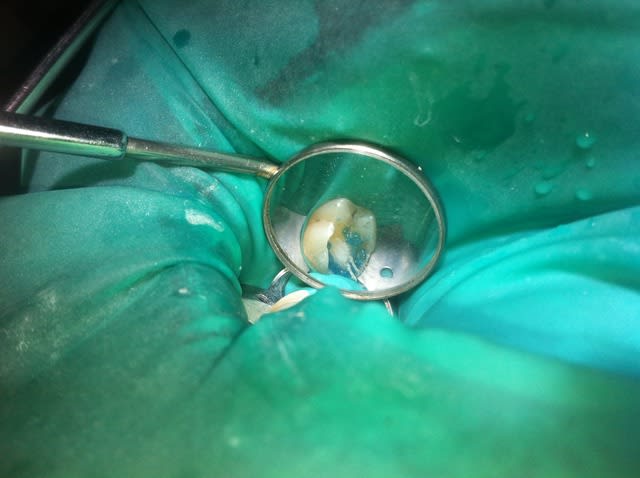

Ben alors j'ai un cas là justement : je fais quoi? Onlay ou Couronne?

Dent vivante, CVI renforcé après la taille en coiffage attente de 3 semaines avec pansement pour être sûr, RAS dent toujours vivante quand je l'ai revu aujourd'hui.

Aujourd'hui : retouche du CVI puis (première photo au stade du mordançage) compo pour le core build-up, pansement.

Les photos sont pas top mais pour le moment je fais avec ce que j'avais sous la main...

Qu'est-ce que je fais pour la suite du coup? Onlay ou Couronne?

PS. On ne voit pas bien la différence à la radio avant-après... Désolé.

Perso je penche pour la couronne...